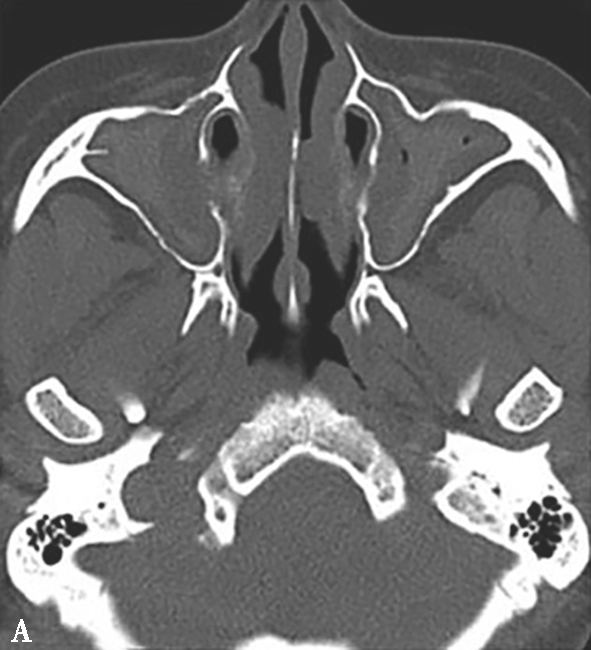

图1-3-22 变应性真菌性鼻窦炎

A、B.横断面、冠状面CT骨窗,示双侧上颌窦、筛窦腔膨胀,窦腔充填软组织密度影,病变内部可见片状磨玻璃样密度增高影,上颌窦壁骨质增生硬化;C.横断面CT软组织窗,示病变内部磨玻璃样密度影显示更清楚

4.CT表现

①平扫表现:半组或全组窦腔内充填软组织影,骨窗示病变内部多发形态不一的云雾状或磨玻璃样密度影,CT值约100HU,软组织窗更为明显,呈不规则线状、匍匐状或斑片状高密度影(图1-3-22);常伴单或双侧鼻息肉;窦腔扩大、窦壁变薄、骨质吸收或结构不清,筛窦最常受累,眶纸板最常见骨质吸收,眶内侵犯多见。②增强扫描表现:边缘黏膜明显强化。

5.MRI表现

①T 1 WI表现:呈低或等信号,外周阻塞炎症多呈低信号。②T 2 WI表现:呈低或极低信号,外周阻塞炎症多呈高信号。③增强扫描表现:病变不强化,增强后外周阻塞炎症周边黏膜明显强化。